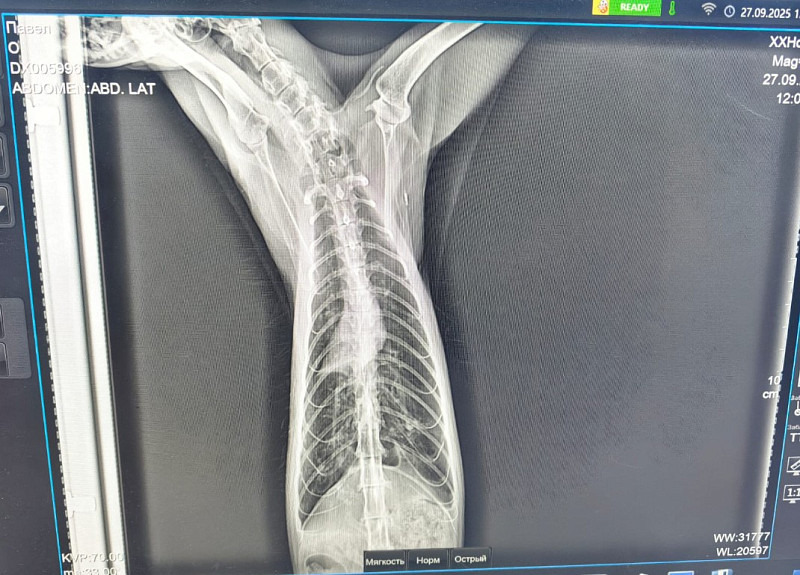

Рентген ориентальной кошки

Помогите разобраться, что с легкими у моего кота, так как вразумительного ответа получить в ветклинике не смог. Может это может то, может астма, может ещё что, а что не понятно. Кот периодически кашляет, хрипит, но в целом, состояние нормальное, нос мокрый, температуры нет, играет. Кашель уже достаточно длительно время стали замечать за ним. Может неделю не кашля, две, хотя может и на глаза нам не попадался. Также могу направить видео его поведения при приступах

здравствуйте, точный диагноз по рентгену невозможен, в данном случае можно только диагностировать прогрессирующее хроническое заболевание бронхов/легких. Для уточнения диагноза необходимо также сделать узи/КТ грудной полости, также нужны анализы крови. Без дополнительной диагностики могут быть назначены только препараты для облегчения кашля. У кошек они как правило в ингаляционной форме.